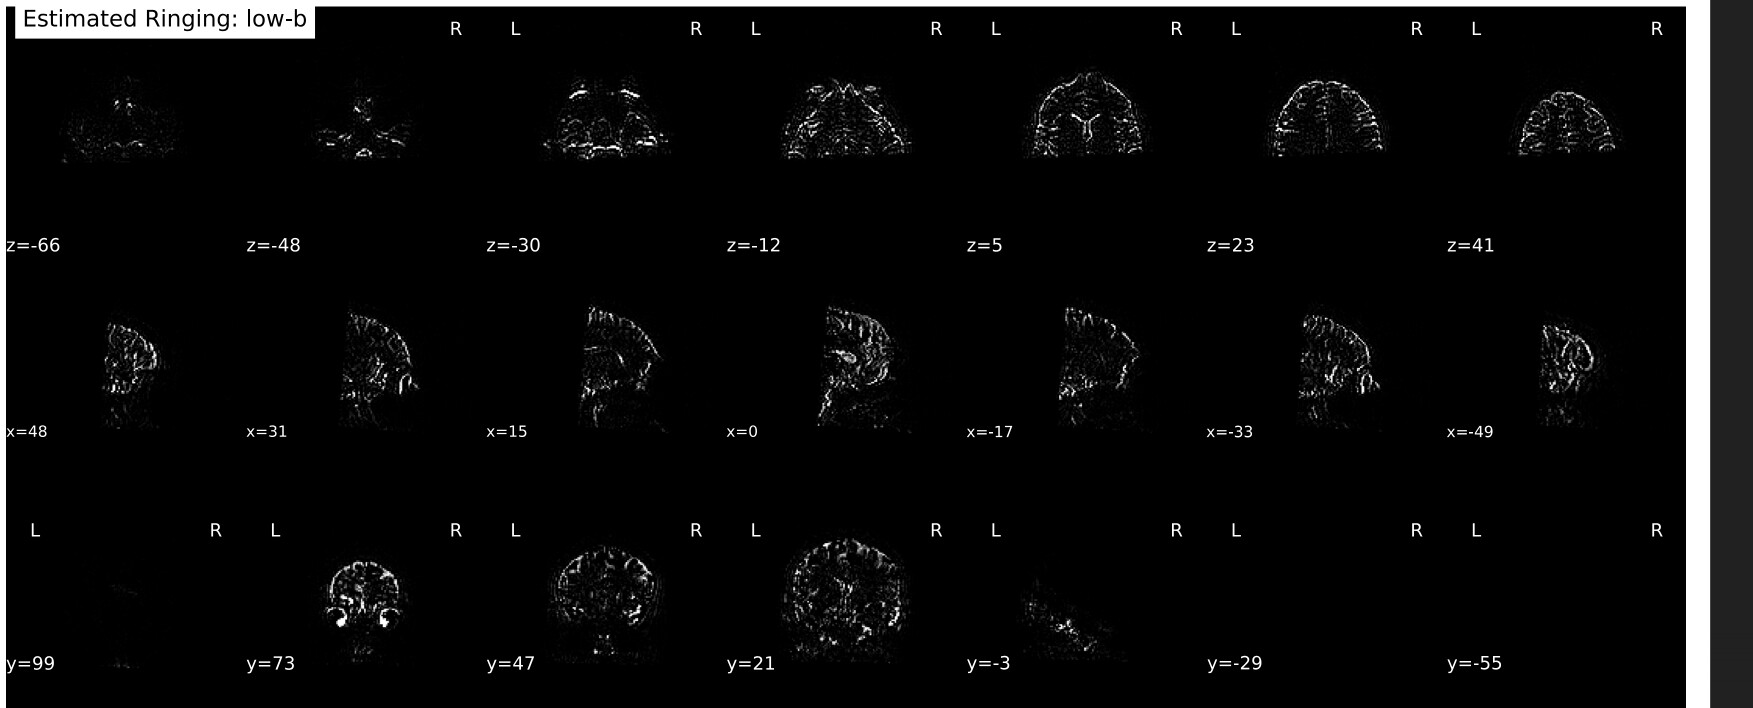

I’ve been processing data for a few different studies using a couple different DSI sequences, two with a multiband Q4 sampling scheme and one multiband cs-DSI—both of which I know @mattcieslak is familiar with (sorry to bother you, Matt). We’ve been noticing that the Gibbs-unringing step in every subject produces some curious outputs: namely, the estimated Gibbs artifacts only appear on the front half of the brain—and I really do mean that literally, insofar as there is a sharp cutoff right at the midpoint of the brain along the phase-encoding axis (see images below).

They are both partial Fourier acquisitions (7/8, so using RPG) with P >> A phase-encoding, so I can rationalize to myself why this could be the case from an acquisition perspective, but given how sharp the transition is, I just want to make sure people smarter than me see this as expected behavior. Will emphasize again this happens in every subject, so as far as I can tell it’s not a random issue arising from head motion or other data quality issues.

An exemplar below (but again, happens for everyone):